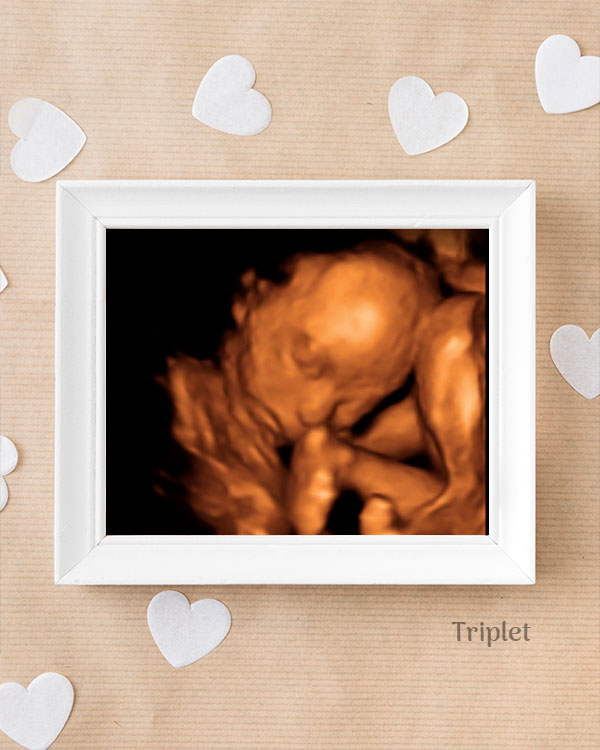

3D / 4D Baby Scan

Mediserv Diagnostics pioneered 4D scanning in the Malabar region. These advanced scans provide realistic images of the baby, allowing detailed evaluation of fetal structures and movements while creating a meaningful bonding experience for parents.